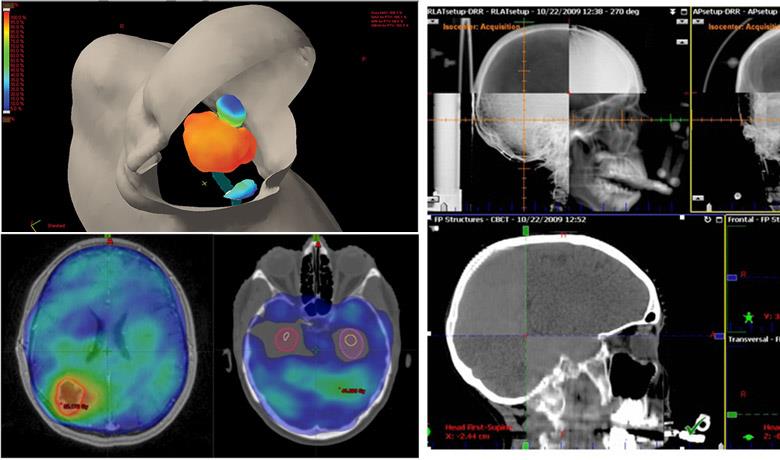

Image Guided Radiotherapy (IGRT) is a technique that performs an image scan of the patient in the treatment position, prior to every radiotherapy session. Imaging is 2D (ExacTrack, Brainlab®, Image 7) or 3D (Cone Beam CT, Image 8). This greatly increases the accuracy of the radiotherapy and reduces the risk of error upon placement of the patient.

IGRT makes radiotherapy more accurate, while lowering the chance of underdosing the tumor or overdosing the normal tissue. It also makes it possible to reduce the necessary margins placed around the tumor to counteract the uncertainties of treatment. As a result, we may decrease the size of the radiation field and consequently irradiate smaller areas of normal tissue, with fewer side-effects for the patients.

Lastly, the great accuracy and the smaller safety margins allow us to deliver large radiation doses daily if necessary, without increasing the risk of toxicity. Large daily doses are delivered by many modern radiotherapy techniques, such as Stereotactic Radiosurgery (SRS).